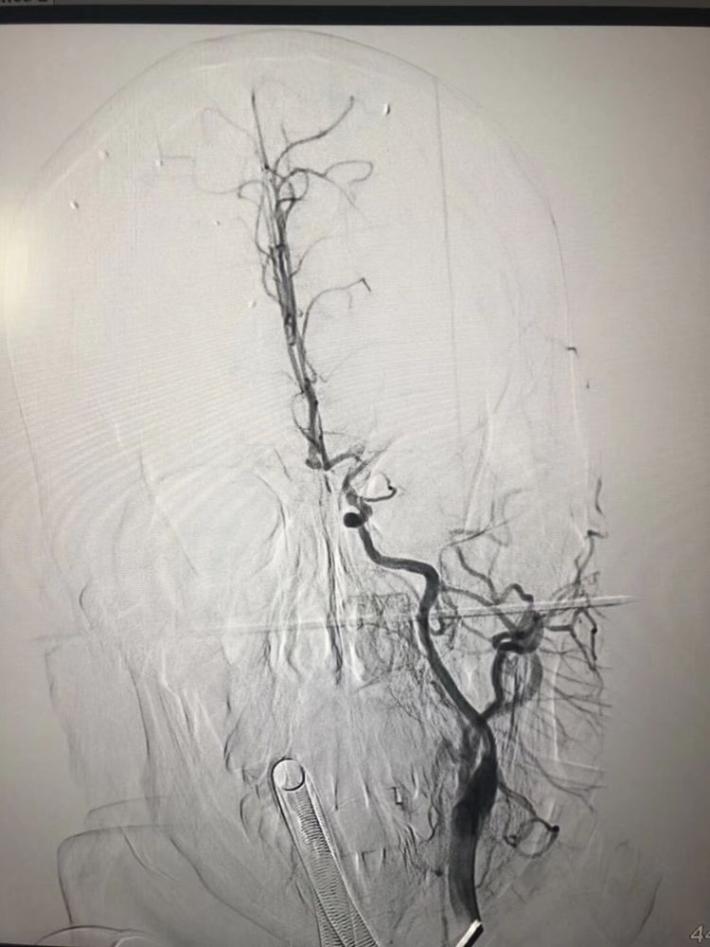

左颈内动脉起始部闭塞,导丝寻到真腔,微导管造影证实远端血管床完整,交换3m导丝,上国产保护伞,球囊扩张颈动脉开口闭塞部位,扩张完,伞被血栓糊住了,前向血流没了,赶紧放颈动脉支架,血流恢复,收伞,伞里一兜血栓,一块血栓堵在大脑中动脉M2,上sab支架取栓,完全再通。